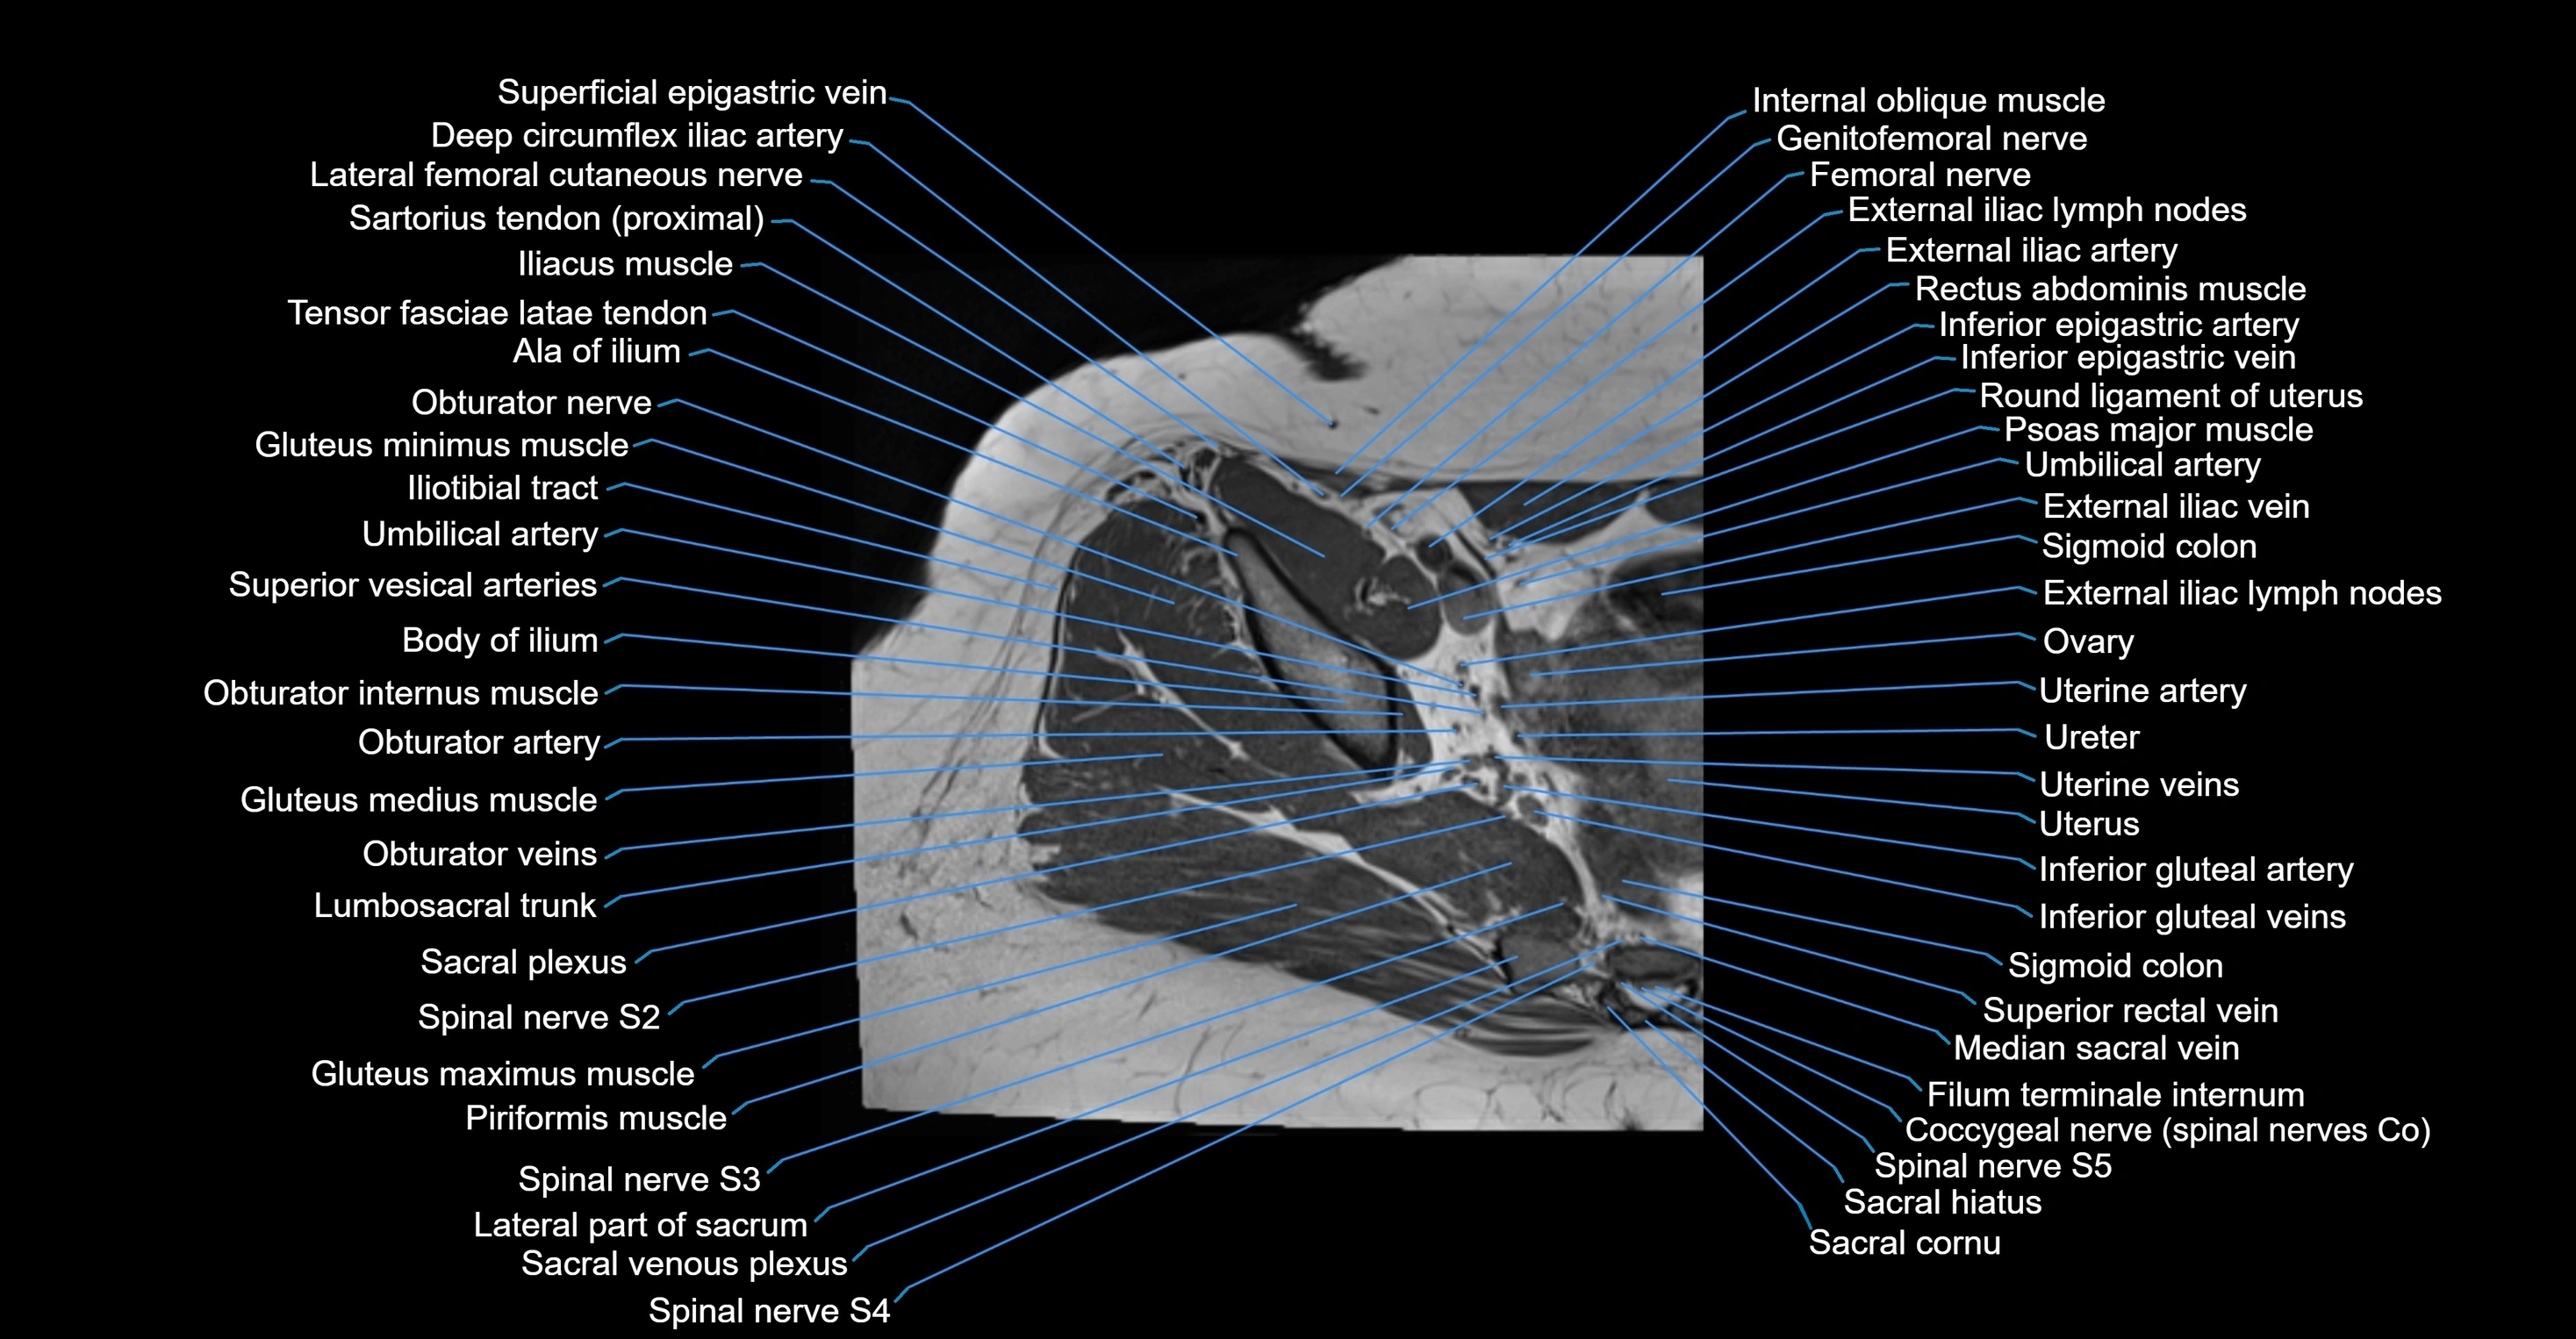

- Common iliac vein

- External iliac artery

- External iliac vein

- Filum terminale internum

- Genitofemoral nerve

- Gluteus maximus muscle

- Gluteus medius muscle

- Inferior epigastric artery

- Inferior epigastric veins

- Inferior gluteal artery

- Inferior gluteal vein

- Lateral part of sacrum

- Lumbosacral trunk

- Median sacral vein

- Median umbilical ligament

- Obturator internus muscle

- Ovaries

- Round ligament of uterus

- Sacral cornu (sacral horn)

- Sacral hiatus

- Sacral plexus

- Sigmoid colon

- Spinal nerve S2

- Spinal nerve S3

- Spinal nerve S4

- Spinal nerve S5

- Superior rectal vein

- Superior vesical artery

- Umbilical artery

- Uterine artery

- Uterus